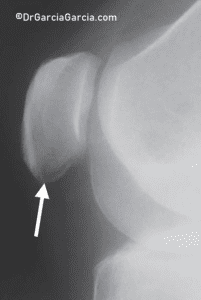

X-rays may reveal changes in the tendon, such as elongation of the inferior pole of the patella, calcification, inferior traction spur (enthesophyte), and increased density within the matrix of the patellar tendon. (fig 9)

Figure 9. Lateral knee X-ray in a case of inferior patellar pole pain. A transverse radiolucent line resembling an avulsion fracture is frequently observed.